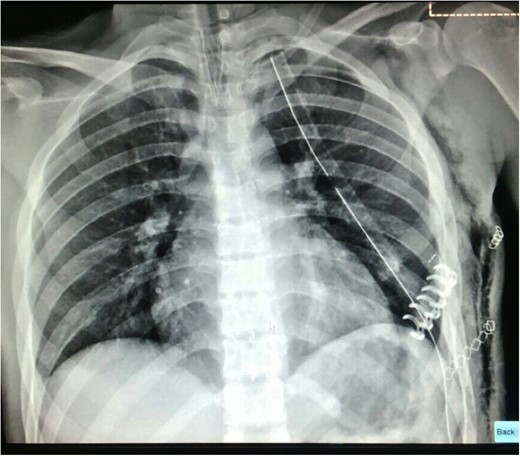

The chest CT showed moderate hemothorax, pneumothorax, a displaced fracture of the fifth left rib, and protrusion of a lung segment through a chest wall defect (Fig. 1).

A chest tube was inserted through the fourth left intercostal space (ICS) and connected to a water seal device (Aquaseal TM) on −20 cm H2O suction.